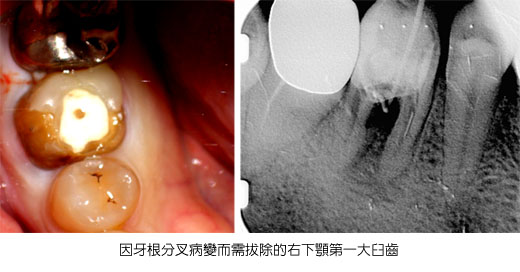

Root Amputation 切除牙根手術 ~ 龍霖 醫師 2012-02-01